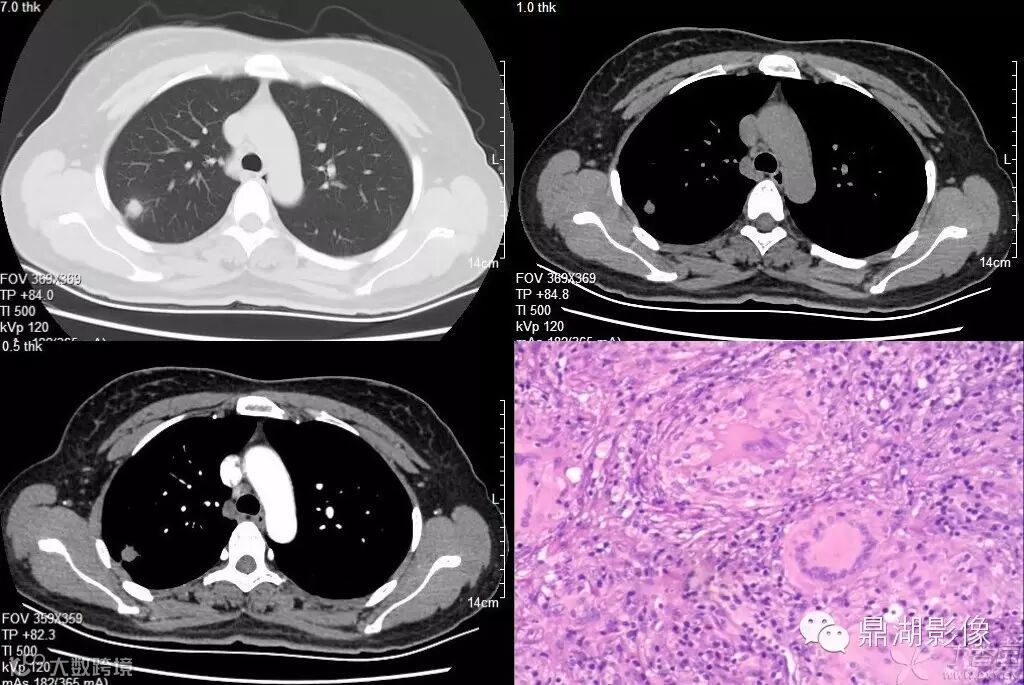

病理结果:脾脏炎性肌纤维母细胞瘤

IMT内不同程度的纤维组织增生,炎性细胞浸润、凝固性坏死已经炎性过程中的动态变化是其影像表现多样性的病理基础。发生于肺内的IMT为单发病灶,多位于肺外周胸膜下,位于邻近胸膜肺组织内,病变边界较清楚,可伴肺不张,密度均匀,病程较长,抗炎治疗复查CT,肿块有缩小趋势。肌纤维母细胞瘤的增强扫描呈均匀或不均匀中度至显著强化,无明显特异性表现。CT扫描呈软组织密度肿块,增强扫描呈均匀或不均匀轻、中度甚至显著强化。之所以出现如此复杂的增强现象,主要是由于组织结构内血管成分不同以及组织成分的不同可出现高度均匀强化、肿块周围强化或肿块无强化,其中肿块高度均匀强化及周围增强程度高于中心部是这种病变较为特征性的表现。

这是一例肺脏的炎性肌纤维母细胞瘤,病灶强化不明显(此图源于丁香园:蓝色宝贝)